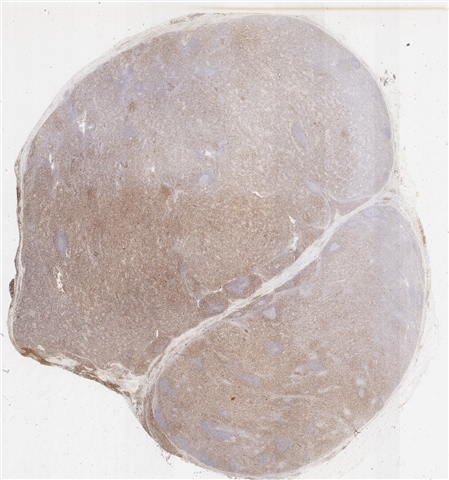

案例5 (6864)

性别:       年龄:62

患者详情: 发现双侧腹股沟肿物1月余。 查体: 双侧腹股沟可扪及多发肿大皮下肿物,大小约2*2cm,质中,边界尚清楚,活动度可,伴压痛,表面皮肤未见红肿破溃。 B超: 双侧腹股沟淋巴结肿大。 病理检查:腹股沟淋巴结穿刺活检提示淋巴组织增生。随行左侧腹股沟淋巴结切除术。

大体所见: 结节状肿物1枚,大小3×2×1.5cm,表面附有包膜,切面灰白灰红色,实性,质中。

医院: 上海长海医院